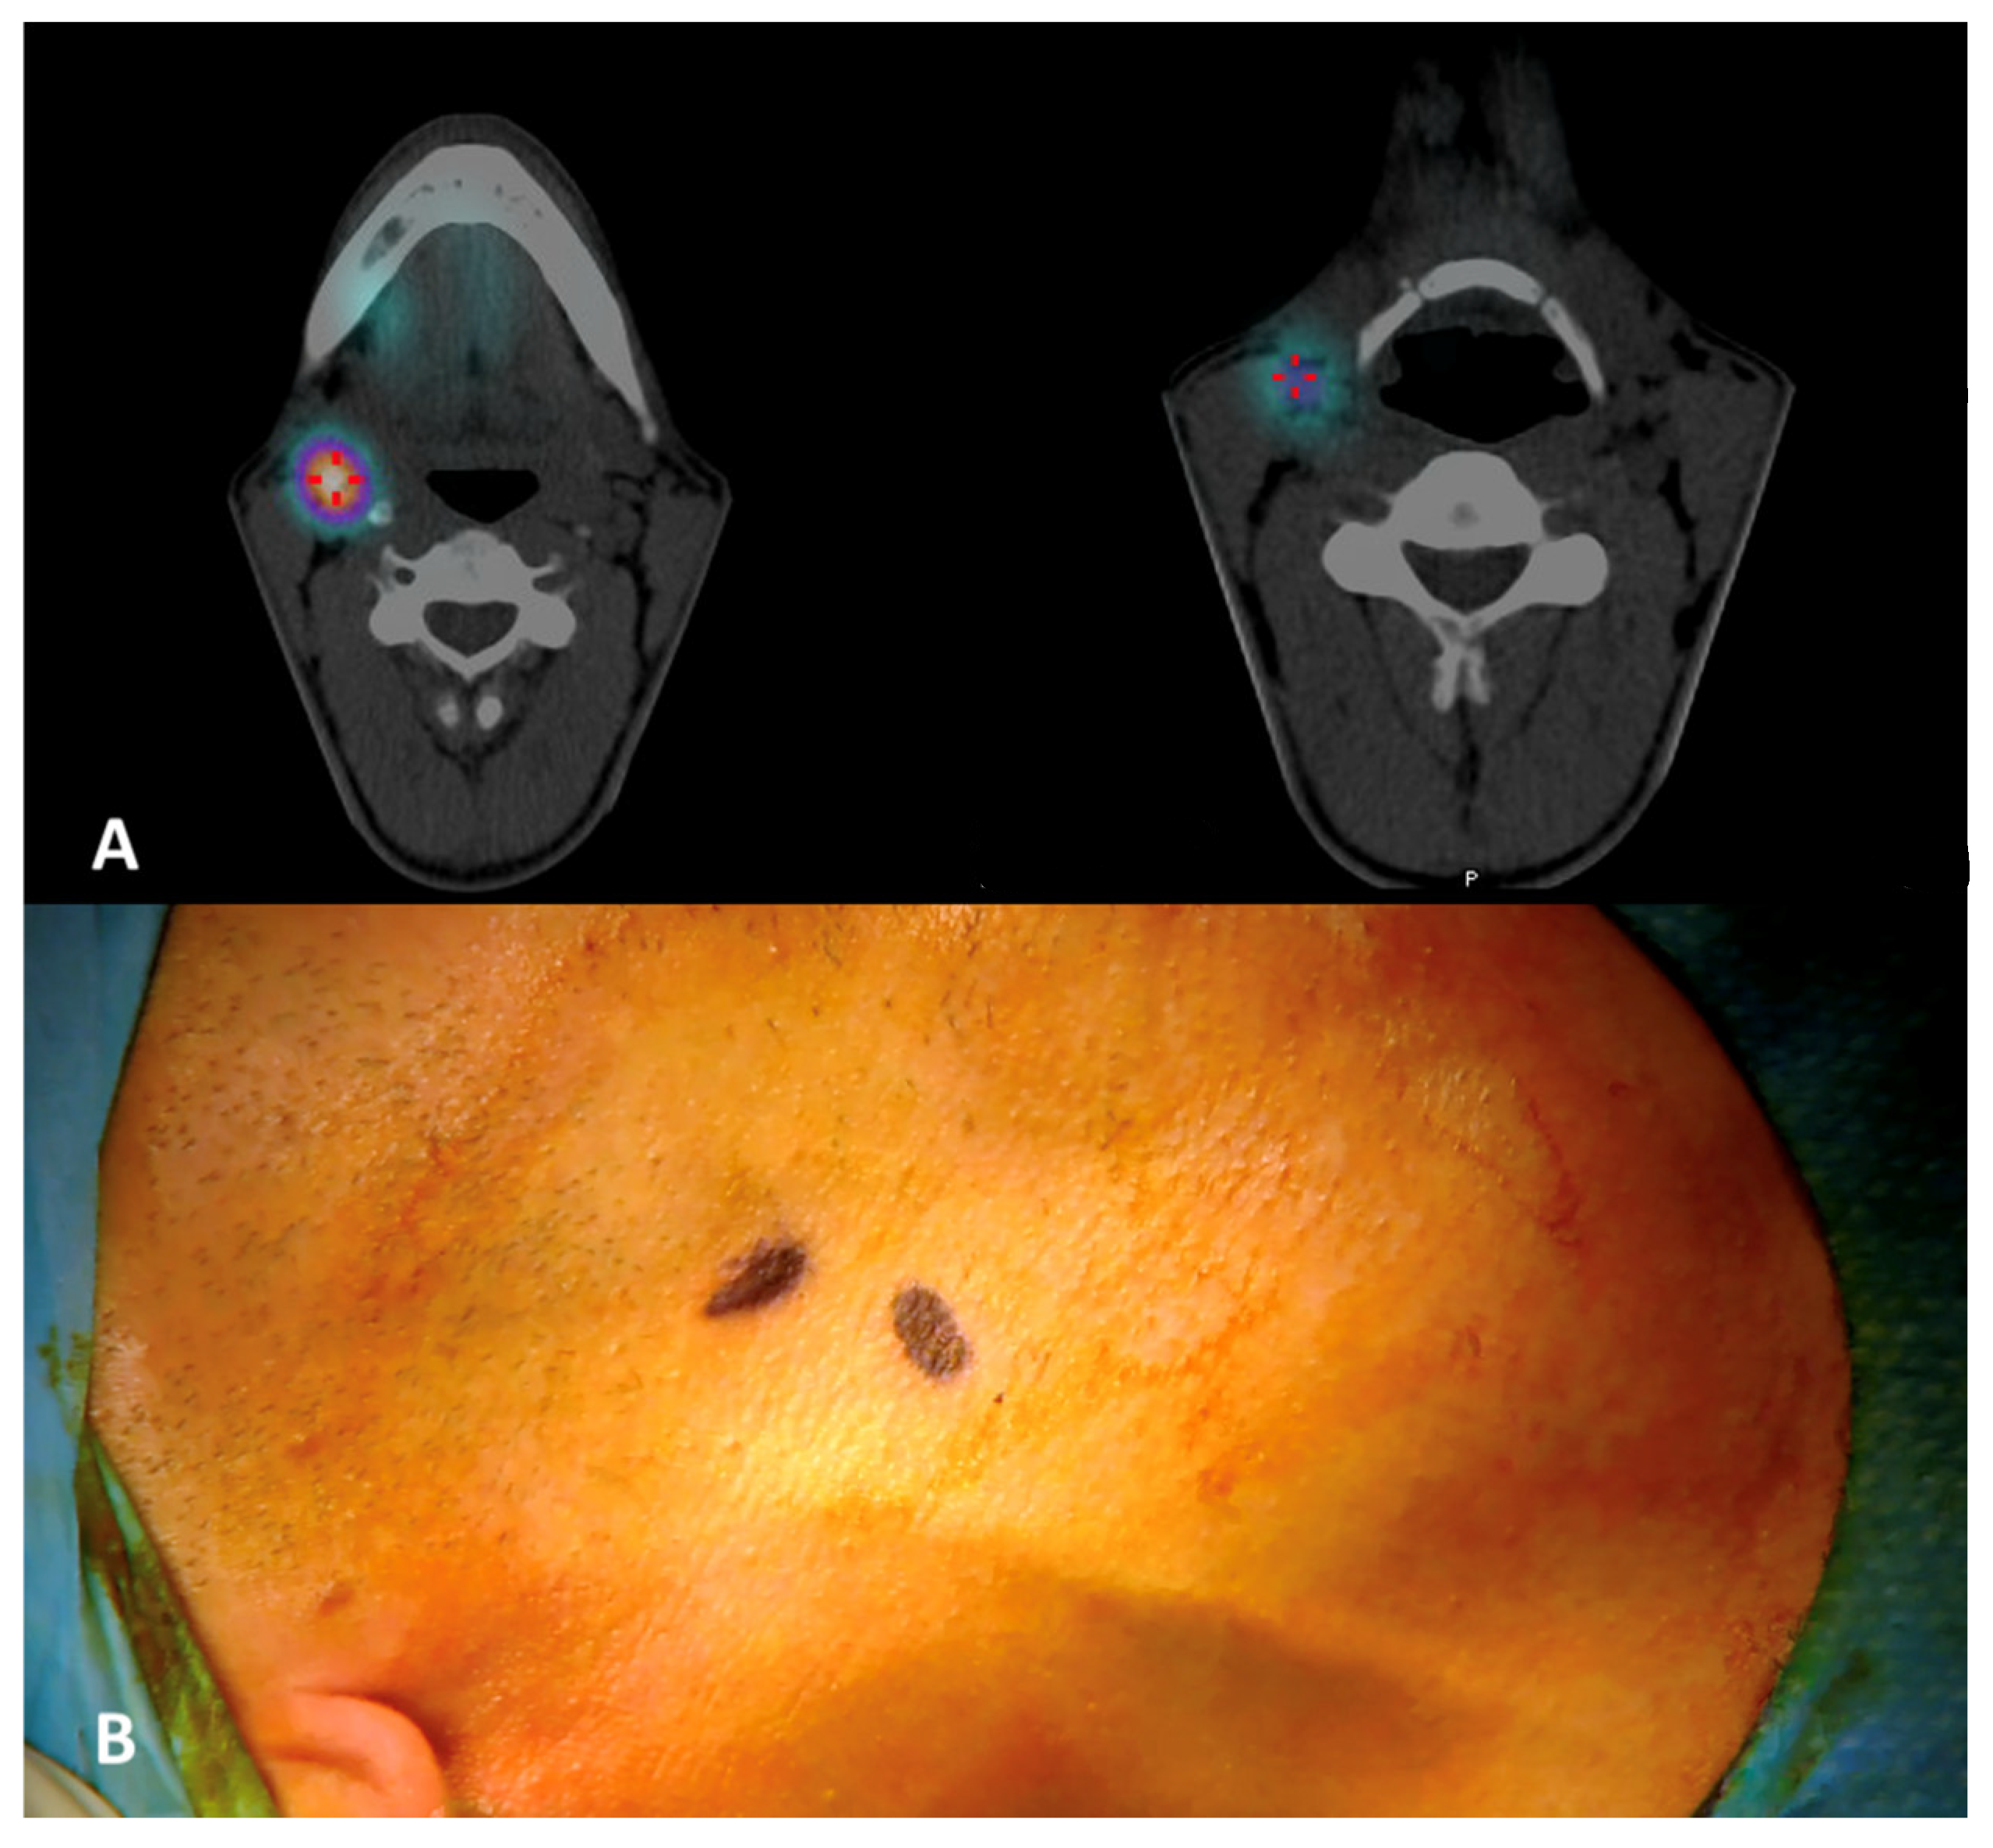

A 34-year-old man with a histologically proven right ventral tongue margin cT1 cN0 SCC was submitted to this protocol. The patient underwent the same preoperative workup, ruling out obvious neck metastases, and a lymphoscintigraphy with 99mTc-Tilmanocept was performed about 4 h before surgery with four submucosal injections around the tumor (0.1 mL per injection, 0.4 mL of total dose, 17 MBq). On planar lymphoscintigraphy and SPECT/CT, two distinct nodal hotspots were identified at levels IIA on the right side: one more cranially at the level of the posterior belly of the digastric muscle, and another one more caudally just above the hyoid bone at the interface between jugulo-digastric and middle jugular nodes (Figure 5). Skin landmarking was performed at the end of procedure with the patient in a surgical position with the head hyperextended to aid subsequent planning. Transoral laser excision (TLE) was performed as initial step (type II glossectomy) [10], again to reduce the expected “shine-through phenomenon” of the injection site on the ventral tongue over the adjacent jugulo-digastric area. ICG was injected at the margins of the tumor bed with four peripheral injections immediately after TLE (2 mL of an ICG-distillated water solution divided in the four injections, with 20 mg of ICG at a 2.0 mg/mL concentration); as highlighted above, a 10-minute window was considered for ICG to drain passively to the specific SLN(s). The same high-resolution NIRF system as before was used (Stryker SPY Pinpoint®) to visualize ICG fluorescence intraoperatively and guide surgical dissection in real time.

Figure 5. (A) Preoperative SPECT/CT with identification of two nodal hotspots (lighter circular areas encircled by a purplish ring) at levels IIA on the right side, one more cranially (left) and one more caudally (right). (B) Skin landmarking.